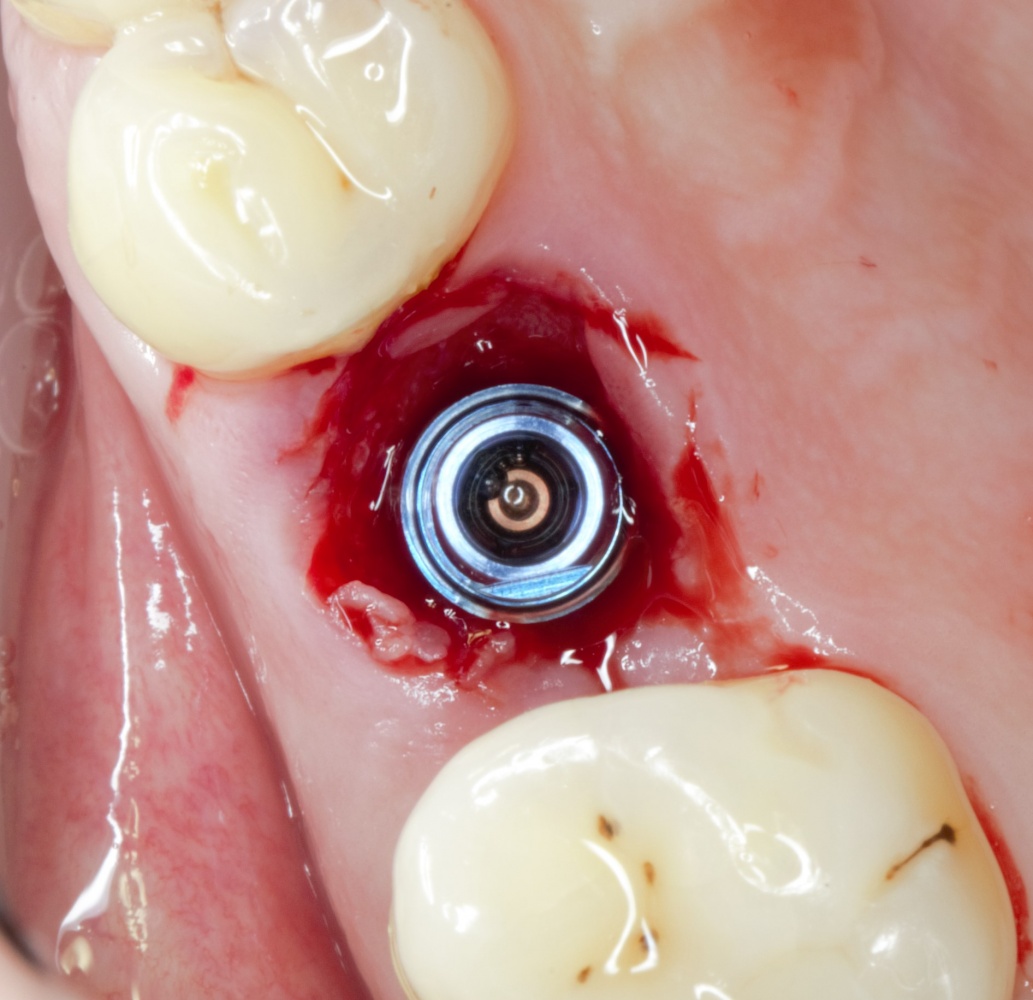

Какими имплантами?

Практически, для проведения операции имплантации одновременно с остеопластикой можно использовать любые импланты. Однако, работа с имплантами, имеющими плоскую ортопедическую платформу (такие, как XiVE Dentsply Implants), несколько сложнее, чем с имплантами, имеющими конический ортопедический интерфейс. Для проведения НКР еще удобнее субкрестальные импланты (к примеру, Ankylos Dentsply Implants), поскольку можно не париться с позиционированием по высоте и просто «утопить» импланты целиком в графт:

A09A5982 (2) A09A5985 (2)  IMG_5560 (2)

Все используемые нами системы имплантов (XiVE, Ankylos, Astratech, Nobel) позволяют беспроблемно проводить остеопластику одновременно с имплантацией и получать хорошие результаты.